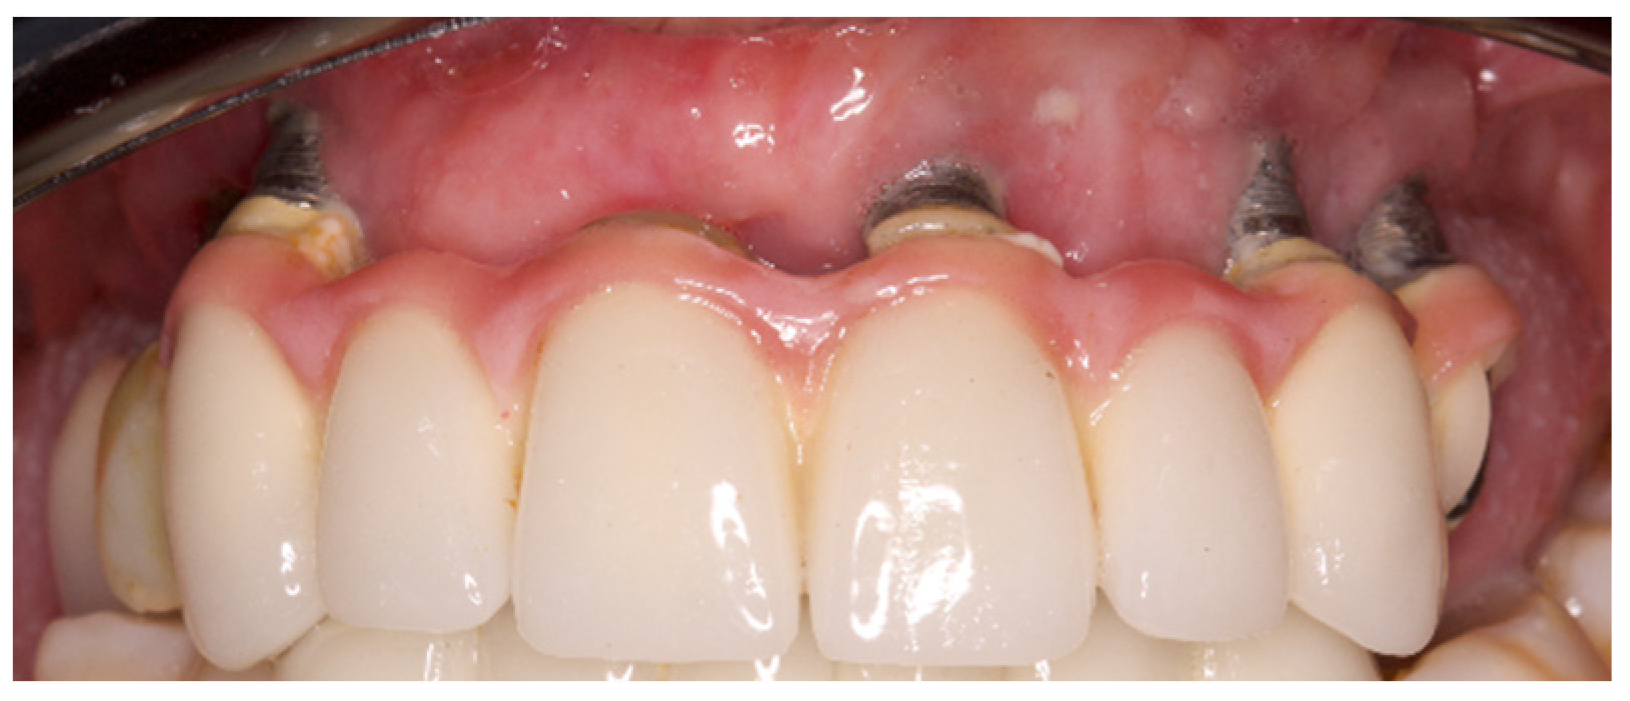

Variables related to the subject were collected; such as age, gender, tobacco consumption and history of periodontitis, as well as variables related to the implants. The main parameter was the presence of keratinized mucosa (KM), as well as the width of KM measured in millimeters in the mid-buccal surface of the implants with a periodontal probe CP 15 from Hu-friedy® (Frankfurt, Germany). The absence of KM was considered when there was non-keratinized mucosa at the gingival margin of the implant (Figure 1). Recession (the apical migration of the gingival margin) was measured in the mid-buccal surface from the cervical margin of the crown, where the gingival margin was located at the time of prosthesis placement. Other parameters were: Silness and Löe plaque index (Figure 2); probing depth using a plastic periodontal probe (Premier®) (at six points: mesiobuccal, buccal, distobuccal, mesiopalatal, palatal and distopalatal) (Figure 3); bleeding (its presence or absence was measured); suppuration (its presence or absence was measured); and bone level (distance, in mm, between the implant shoulder and the base of the defect) using Rhinoceros® software (Robert Mcneel & Associates, Seattle, WA, USA) on the parallelized radiographs. Bone loss due to peri-implantitis was considered when a crater-shaped image was observed surrounding the implant (taking as reference the most apical area of the crater) (Figure 4), accompanied by clinical signs such as bleeding or suppuration. The years since prosthesis placement were also noted. All data were collected by a single operator who visually analyzed the esthetics of the peri-implant tissues.

Figure 2.

Silness and Löe plaque index (PI = 3 in 2.3 and 2.4, PI = 2 in 1.3 and 2.1).